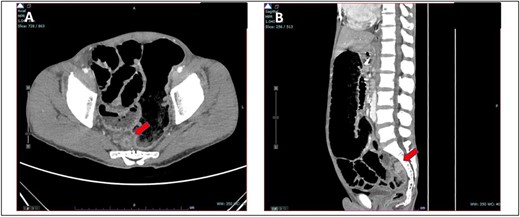

He presented with a history of abdominal distension for 1 week, loose stool, and vomiting for 3 days. Since admission to the ward, he had no bowel opening and did not pass flatus. On examination, he appeared dehydrated, and his abdomen was soft but distended. Plain abdominal radiograph showed dilated bowel. Computed tomography of the abdomen and pelvis showed short segment thickening of proximal transverse colon with dilatation bowel proximally, enlargement of mesenteric nodes, and mild ascites (Fig. 1). We proceeded with exploratory laparotomy, right hemicolectomy, and double barrel stoma. Intraoperatively, a noted tumour at proximal transverse colon size of about 5 × 4 cm with proximal bowel dilatation and distally bowel collapsed. Multiple mesocolic nodes were also present.

(A) Axial view and (B) coronal view of computed tomography showed short segment thickening of proximal transverse colon (red arrow) with dilatation of bowel.